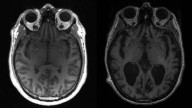

“ ...HAVERÁ PESTES” (Mt 24,7) Doença neurológica bizarra aflige jovens canadenses